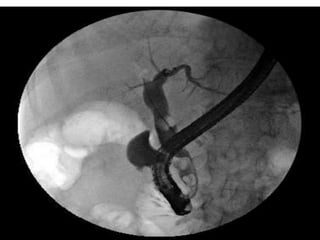

PTC

 The catheter is placed

into the intrahepatic

bile duct through

patient’s skin guided

by US and fixed on the

skin.

 The radiographic image

is then taken.

 Obstructive lesion can

be seen .